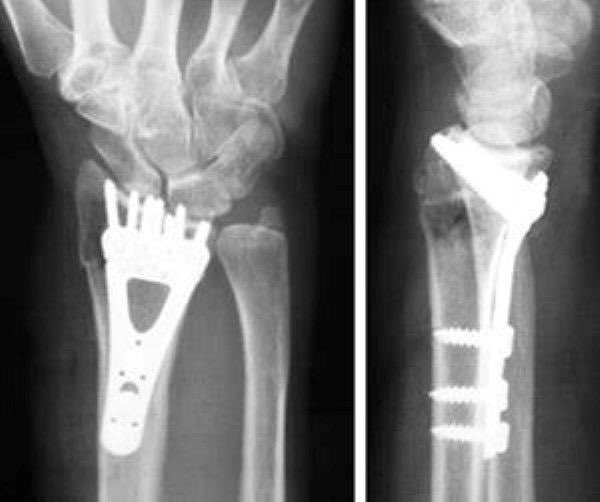

🔹 الشد المفتوح والتثبيت الداخلي باستخدام البراغي والصفائح المعدنية للبالغين (Open reduction and internal fixation)، أما للأطفال تستخدم أسياخ تسمى "K wire”.

🔹 التثبيت الخارجي (External fixation):

يستخدم في حال وجود تهتك كبير بأنسجة العظم والجلد، يتم زراعة مسامير فوق وتحت خط الكسر، ومن ثم ربط أطراف المسامير الخارجية بدعامات خاصة. يساعد هذا الهيكل على تثبيت القطع المكسورة حتى اكتمال التئام الكسور ثم يتم إجراء التثبيت الداخلي بالشرائح.

🔹 بعد الجراحة يجب التأكد من تثبيت مفصل الرسغ مع المِرفق، يحتاج التعافي إلى ٦ أسابيع على الأقل وقد تمتد إلى ١٠ أسابيع، و يمكن إزالة الشرائح الداخلية للبالغين بعد مدة من التحام للعظام أما الأطفال بعد ٤ أسابيع من التثبيت.